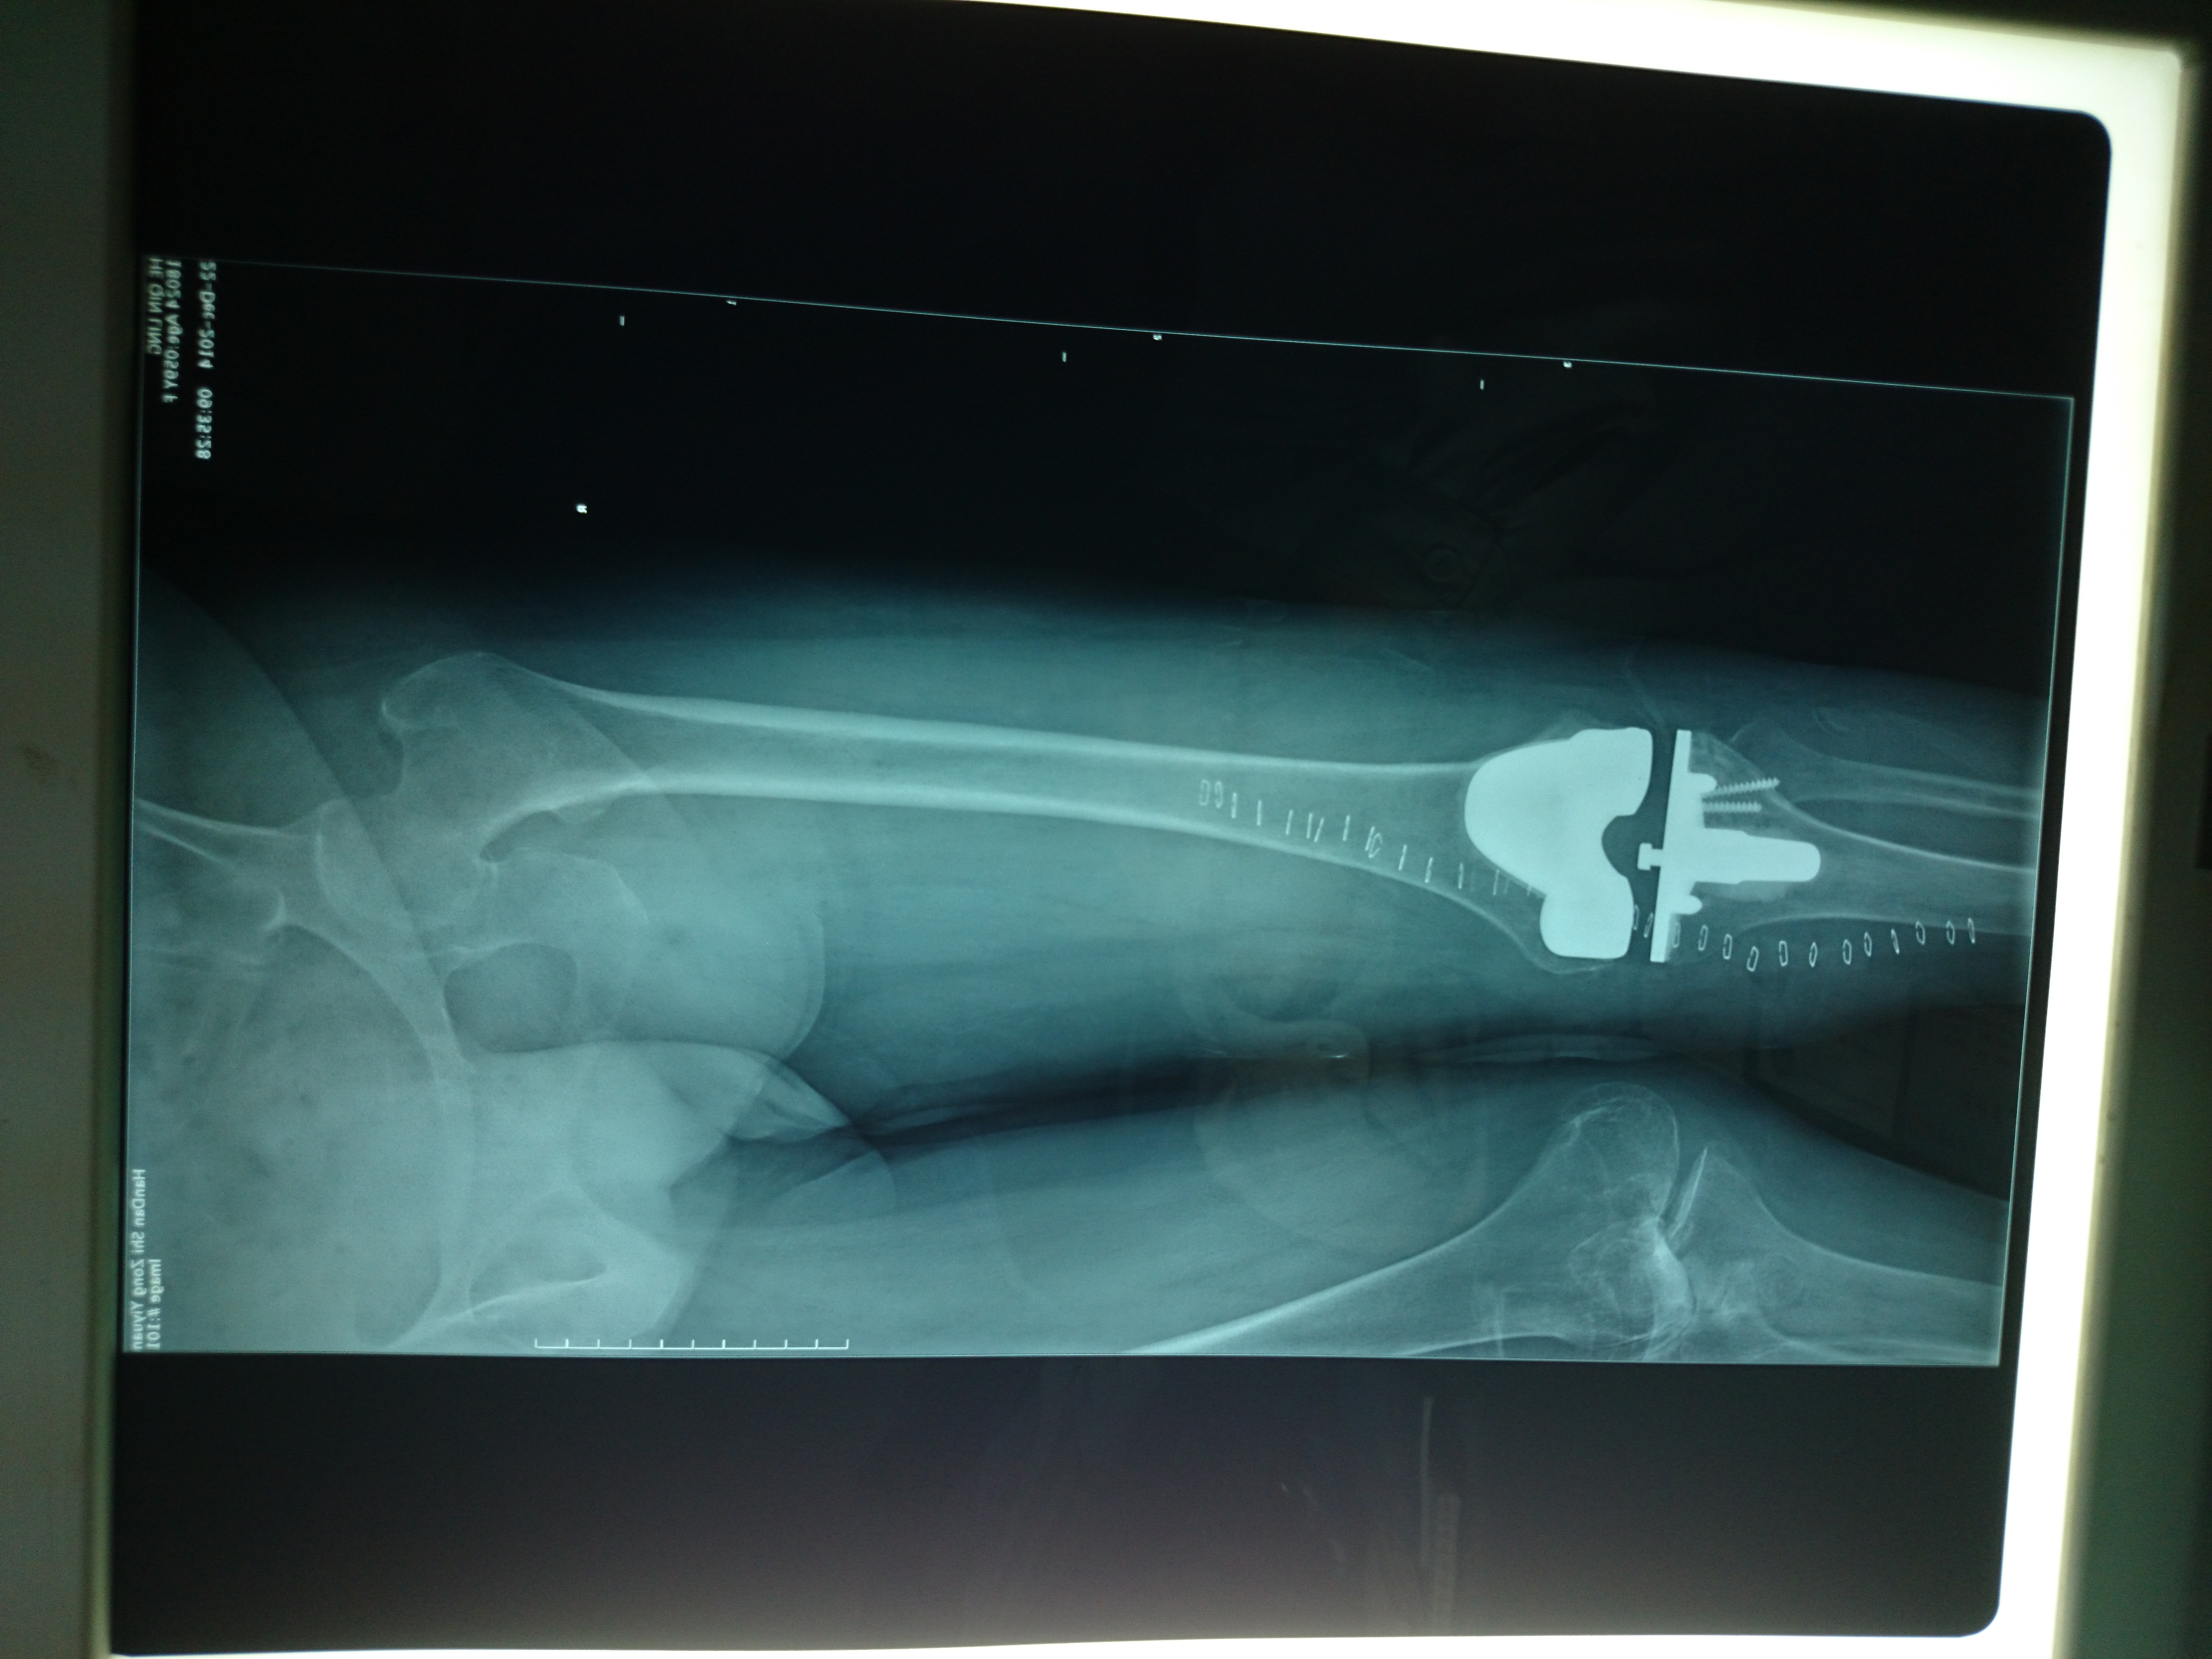

首页 > 张恒云工作室 > 影像资料 二十二